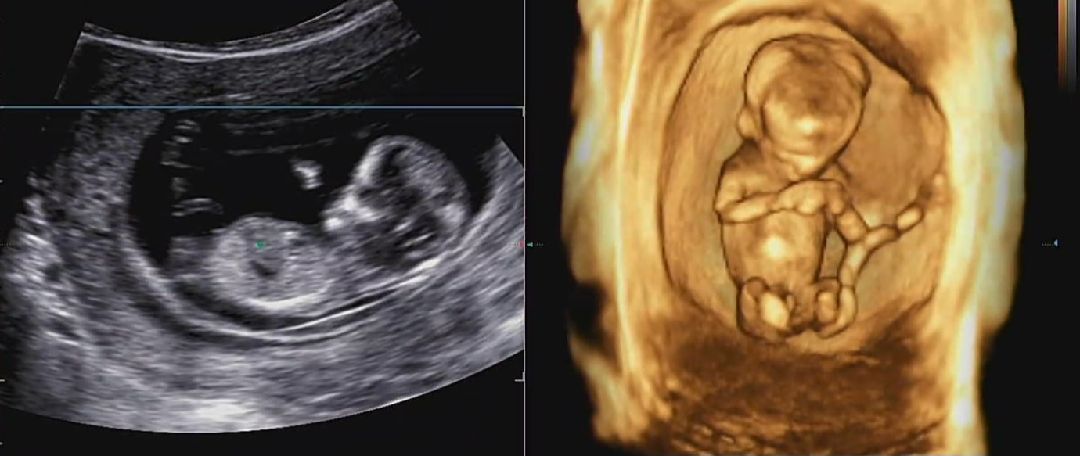

안녕하세요 12주차 예비아빠입니당^^ 오늘 초음파사진과 입체초음파를 보는데 가운데에 🌶 같은게 보여서 남자아이인것같은데, 의사선생님은 16주에 알려주실수 있다고 하시네요...ㅎㅎ 혹시 여러분들은 성별이 어떻게 보이시나요~~